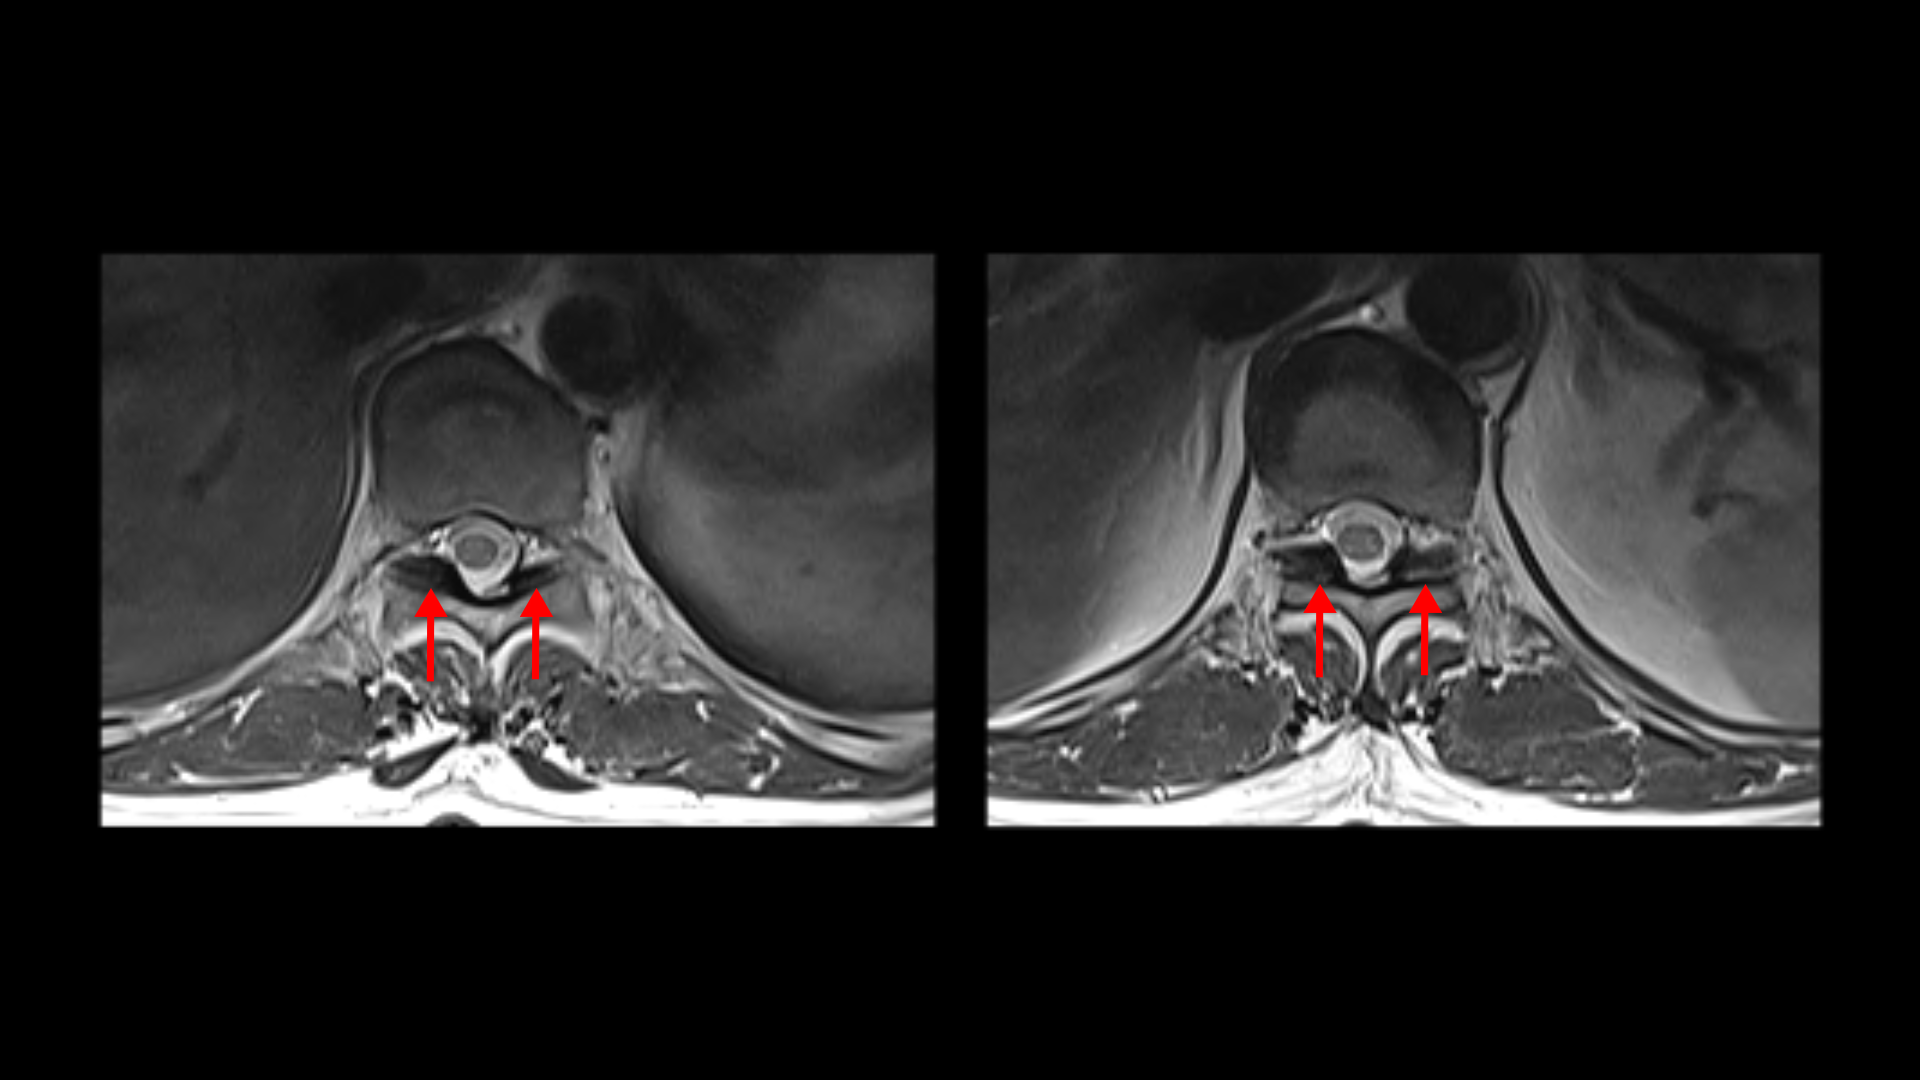

또 흉추 두 마디에서도 역시 황색인대의 골화 현상이 보입니다.